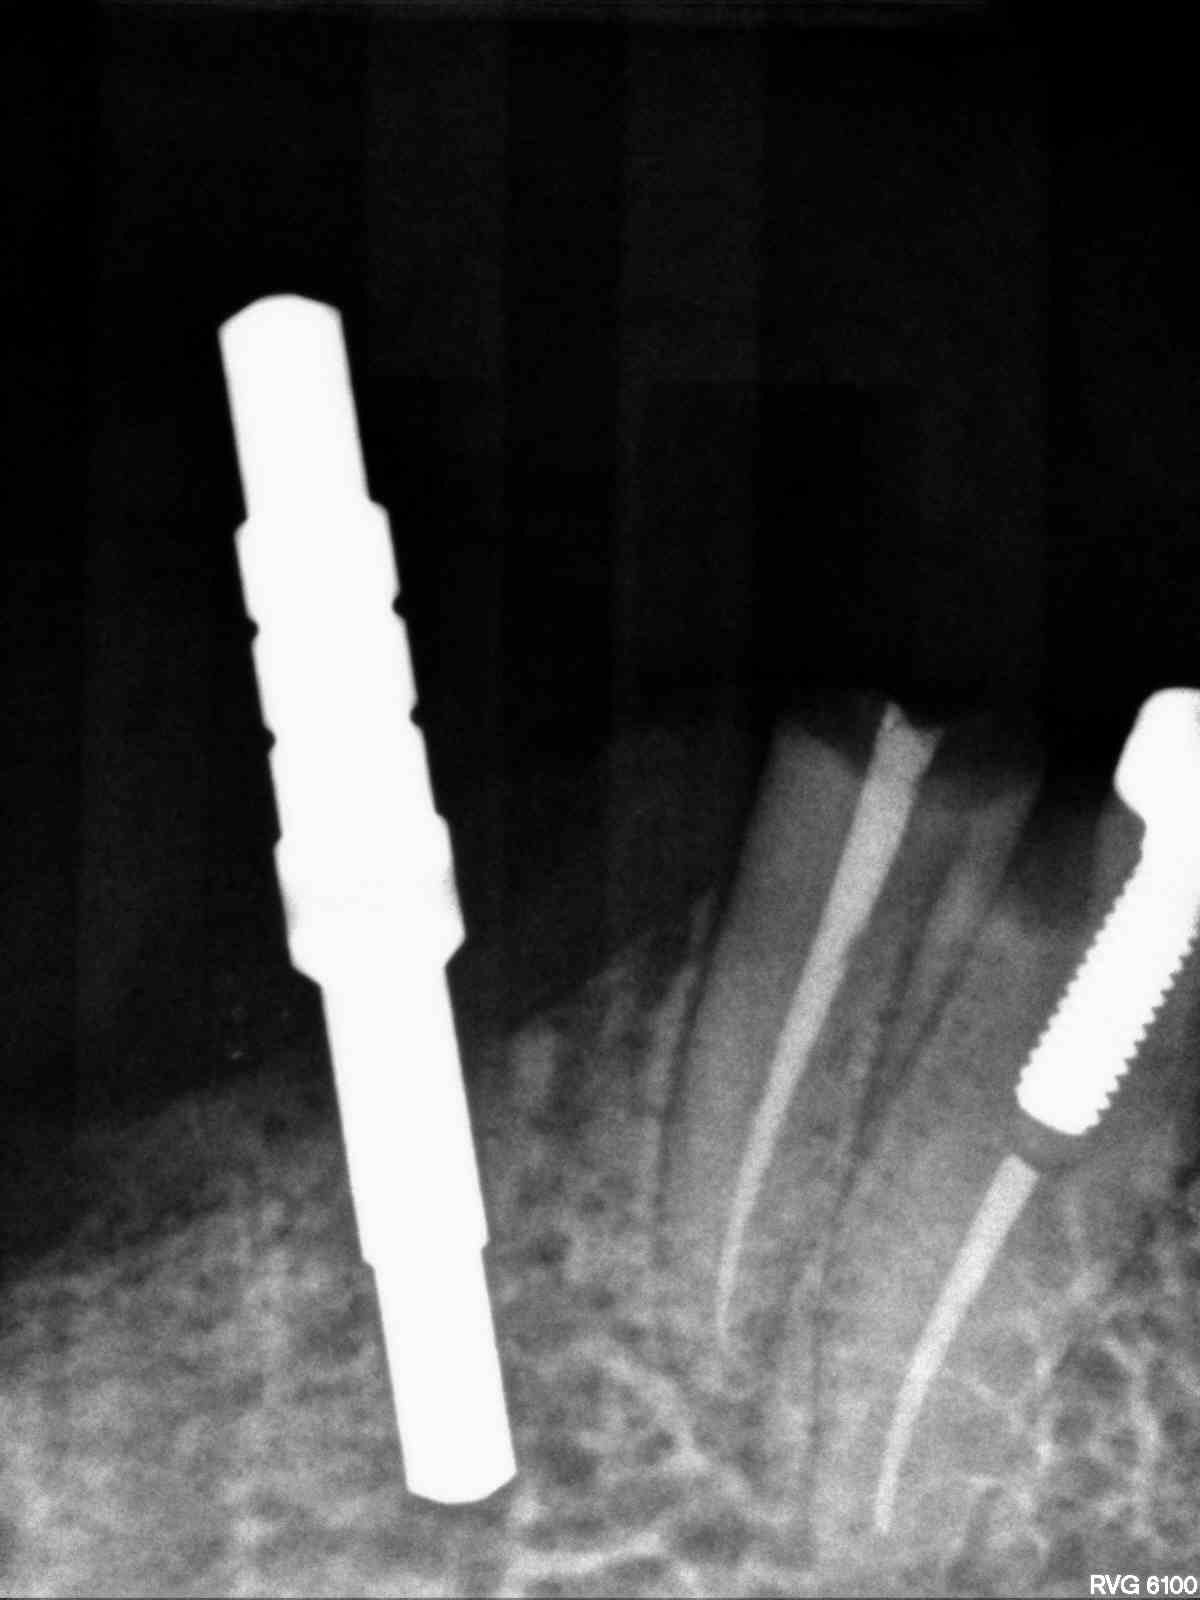

Legacy 3 3.7mm 11.5mm

implanted r4

Implant for locator retained denture

Immediate #21 Legacy 3 4.2x13mm

Legacy 3 #7 3.7mm 13mm